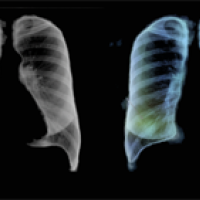

Chest X-ray images which have been pre-processed so an AI algorithm finds them easier to analyse.

For example, it may learn the font the hospital uses to label X-ray images with patients' names, and decide that whenever an image has that font in its labelling, the corresponding patient has COVID-19. One way of getting around this problem is to pre-process X-ray images so that potentially confounding patterns are removed. The AIX-COVNET team have been exploring viable techniques for doing this.